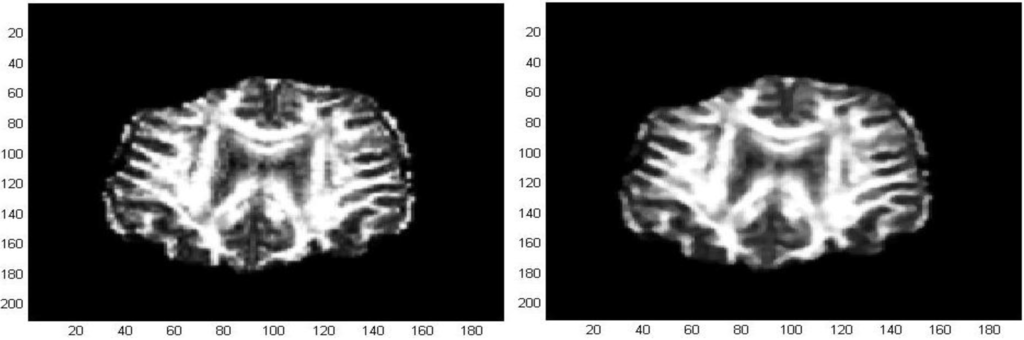

The first processed GM image (Figure 11) refers to a subject of the control group (see the first image of Figure 12). The force field has been evaluated from Equation (9) after eight iterations, the overlapping green curves represent initial contours that are automatically selected from the contour map of divergence. In Figure 13 and Figure 14 we have treated GM images derived from two patients affected by Alzheimer’s disease and they refer respectively to the second and third images which are shown in Figure 12. Once edges are detected, we produce a boundary representation of gray matter that can be used for an automatic analysis of shapes from the geometrical, metrical or morphological point of view.

Figure 12. GM images for a subject of the control group and two patients affected by Alzheimer’s disease.

Algorithms 05 00636 g012